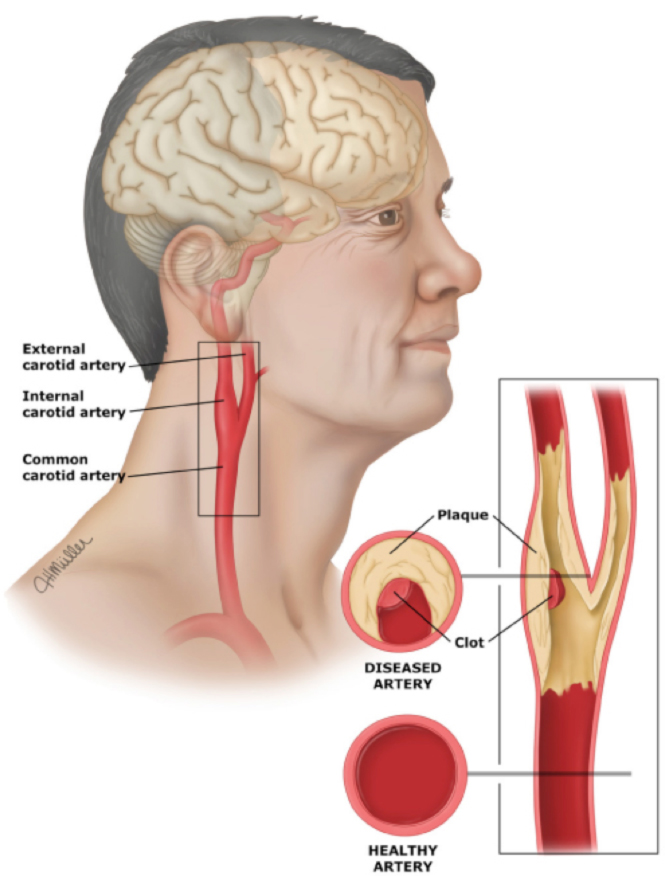

TCAR Procedure Savannah Vascular Institute

Carotid Artery Disease Stroke Victorian Vascular

Carotid Artery Disease CAD

Carotid Artery Stenosis Wikidoc

Carotid Arteries Eye Patient

The Warning Signs Of Clogged Arteries Heart Blockage Clogged

Carotid Artery Stenosis Wikidoc

Occluded Carotid Artery Carotisverengung Swiss Surgery

Carotid Artery Pain Symptoms

Carotid Artery Pain Symptoms

Carotid Artery Pain Symptoms

Carotid Artery Pain Symptoms